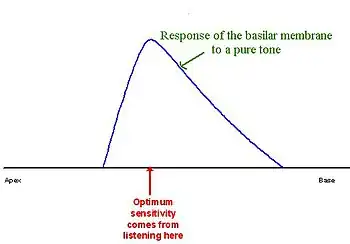

The traveling wave along the basilar membrane peaks at different places along it, depending on whether the sound is low or high frequency. Due to the mass and stiffness of the basilar membrane, low frequency waves peak in the apex, while high frequency sounds peak in the basal end of the cochlea.[13] Therefore, each position along the basilar membrane is finely tuned to a particular frequency. These specifically tuned frequencies are referred to as characteristic frequencies (CF).[14]

If a sound entering the ear is displaced from the characteristic frequency, then the strength of response from the basilar membrane will progressively lessen. The fine tuning of the basilar membrane is created by the input of two separate mechanisms. The first mechanism being a linear passive mechanism, which is dependent on the mechanical structure of the basilar membrane and its surrounding structures. The second mechanism is a non-linear active mechanism, which is primarily dependent on the functioning of the OHCs, and also the general physiological condition of the cochlea itself. The base and apex of the basilar membrane differ in stiffness and width, which cause the basilar membrane to respond to varying frequencies differently along its length. The base of the basilar membrane is narrow and stiff, resulting in it responding best to high frequency sounds. The apex of the basilar membrane is wider and much less stiff in comparison to the base, causing it to respond best to low frequencies.[14]

This selectivity to certain frequencies can be illustrated by neural tuning curves. These demonstrate the frequencies a fiber responds to, by showing threshold levels (dB SPL) of auditory nerve fibers as a function of different frequencies. This demonstrates that auditory nerve fibers respond best, and hence have better thresholds at the fiber's characteristic frequency and frequencies immediately surrounding it. The basilar membrane is said to be ‘sharply tuned’ due to the sharp ‘V’ shaped curve, with its ‘tip’ centered at the auditory fibers characteristic frequency. This shape shows how few frequencies a fiber responds to. If it were a broader ‘V’ shape, it would be responding to more frequencies (See Figure 4).[13]

However, it appears that this is not the case. Dead regions cannot be clearly found via PTA audiograms. This may be because although the neurons innervating the dead region, cannot react to vibration at their characteristic frequency. If the basilar membrane vibration is large enough, neurons tuned to different characteristic frequencies such as those adjacent to the dead region, will be stimulated due to the spread of excitation. Therefore, a response from the patient at the test frequency will be obtained. This is referred to as “off-place listening”, and is also known as ‘off-frequency listening’. This will lead to a false threshold being found. Thus, it appears a person has better hearing than they actually do, resulting in a dead region being missed. Therefore, using PTA alone, it is impossible to identify the extent of a dead region (See Figure 7 and 8).[15]